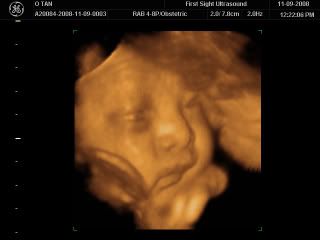

The very first picture of him with his eyes wide open... Darling says Caleb looks like me! He has my nose! The first thing I said when I saw baby Caleb was, "He has such chubby cheeks!" Haha... It seems like he's gonna be a big baby, just like me and Jason when we were babies! Oops... Can you see his open eyes?